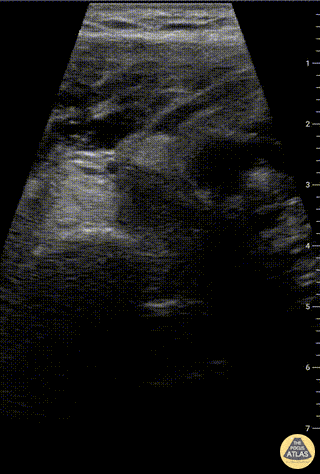

Musculoskeletal - Humeral head fracture with traumatic effusion

Patient fell onto his left shoulder with point tenderness at the proximal humeral neck. Point-of-care ultrasound showed cortical break on a transverse view of the humeral head. Hyperechoic fluid was visualized in the glenohumeral joint, likely clotted blood. A comminuted humeral head/neck fracture was confirmed on XR. Charles Jang, EM PGY-3